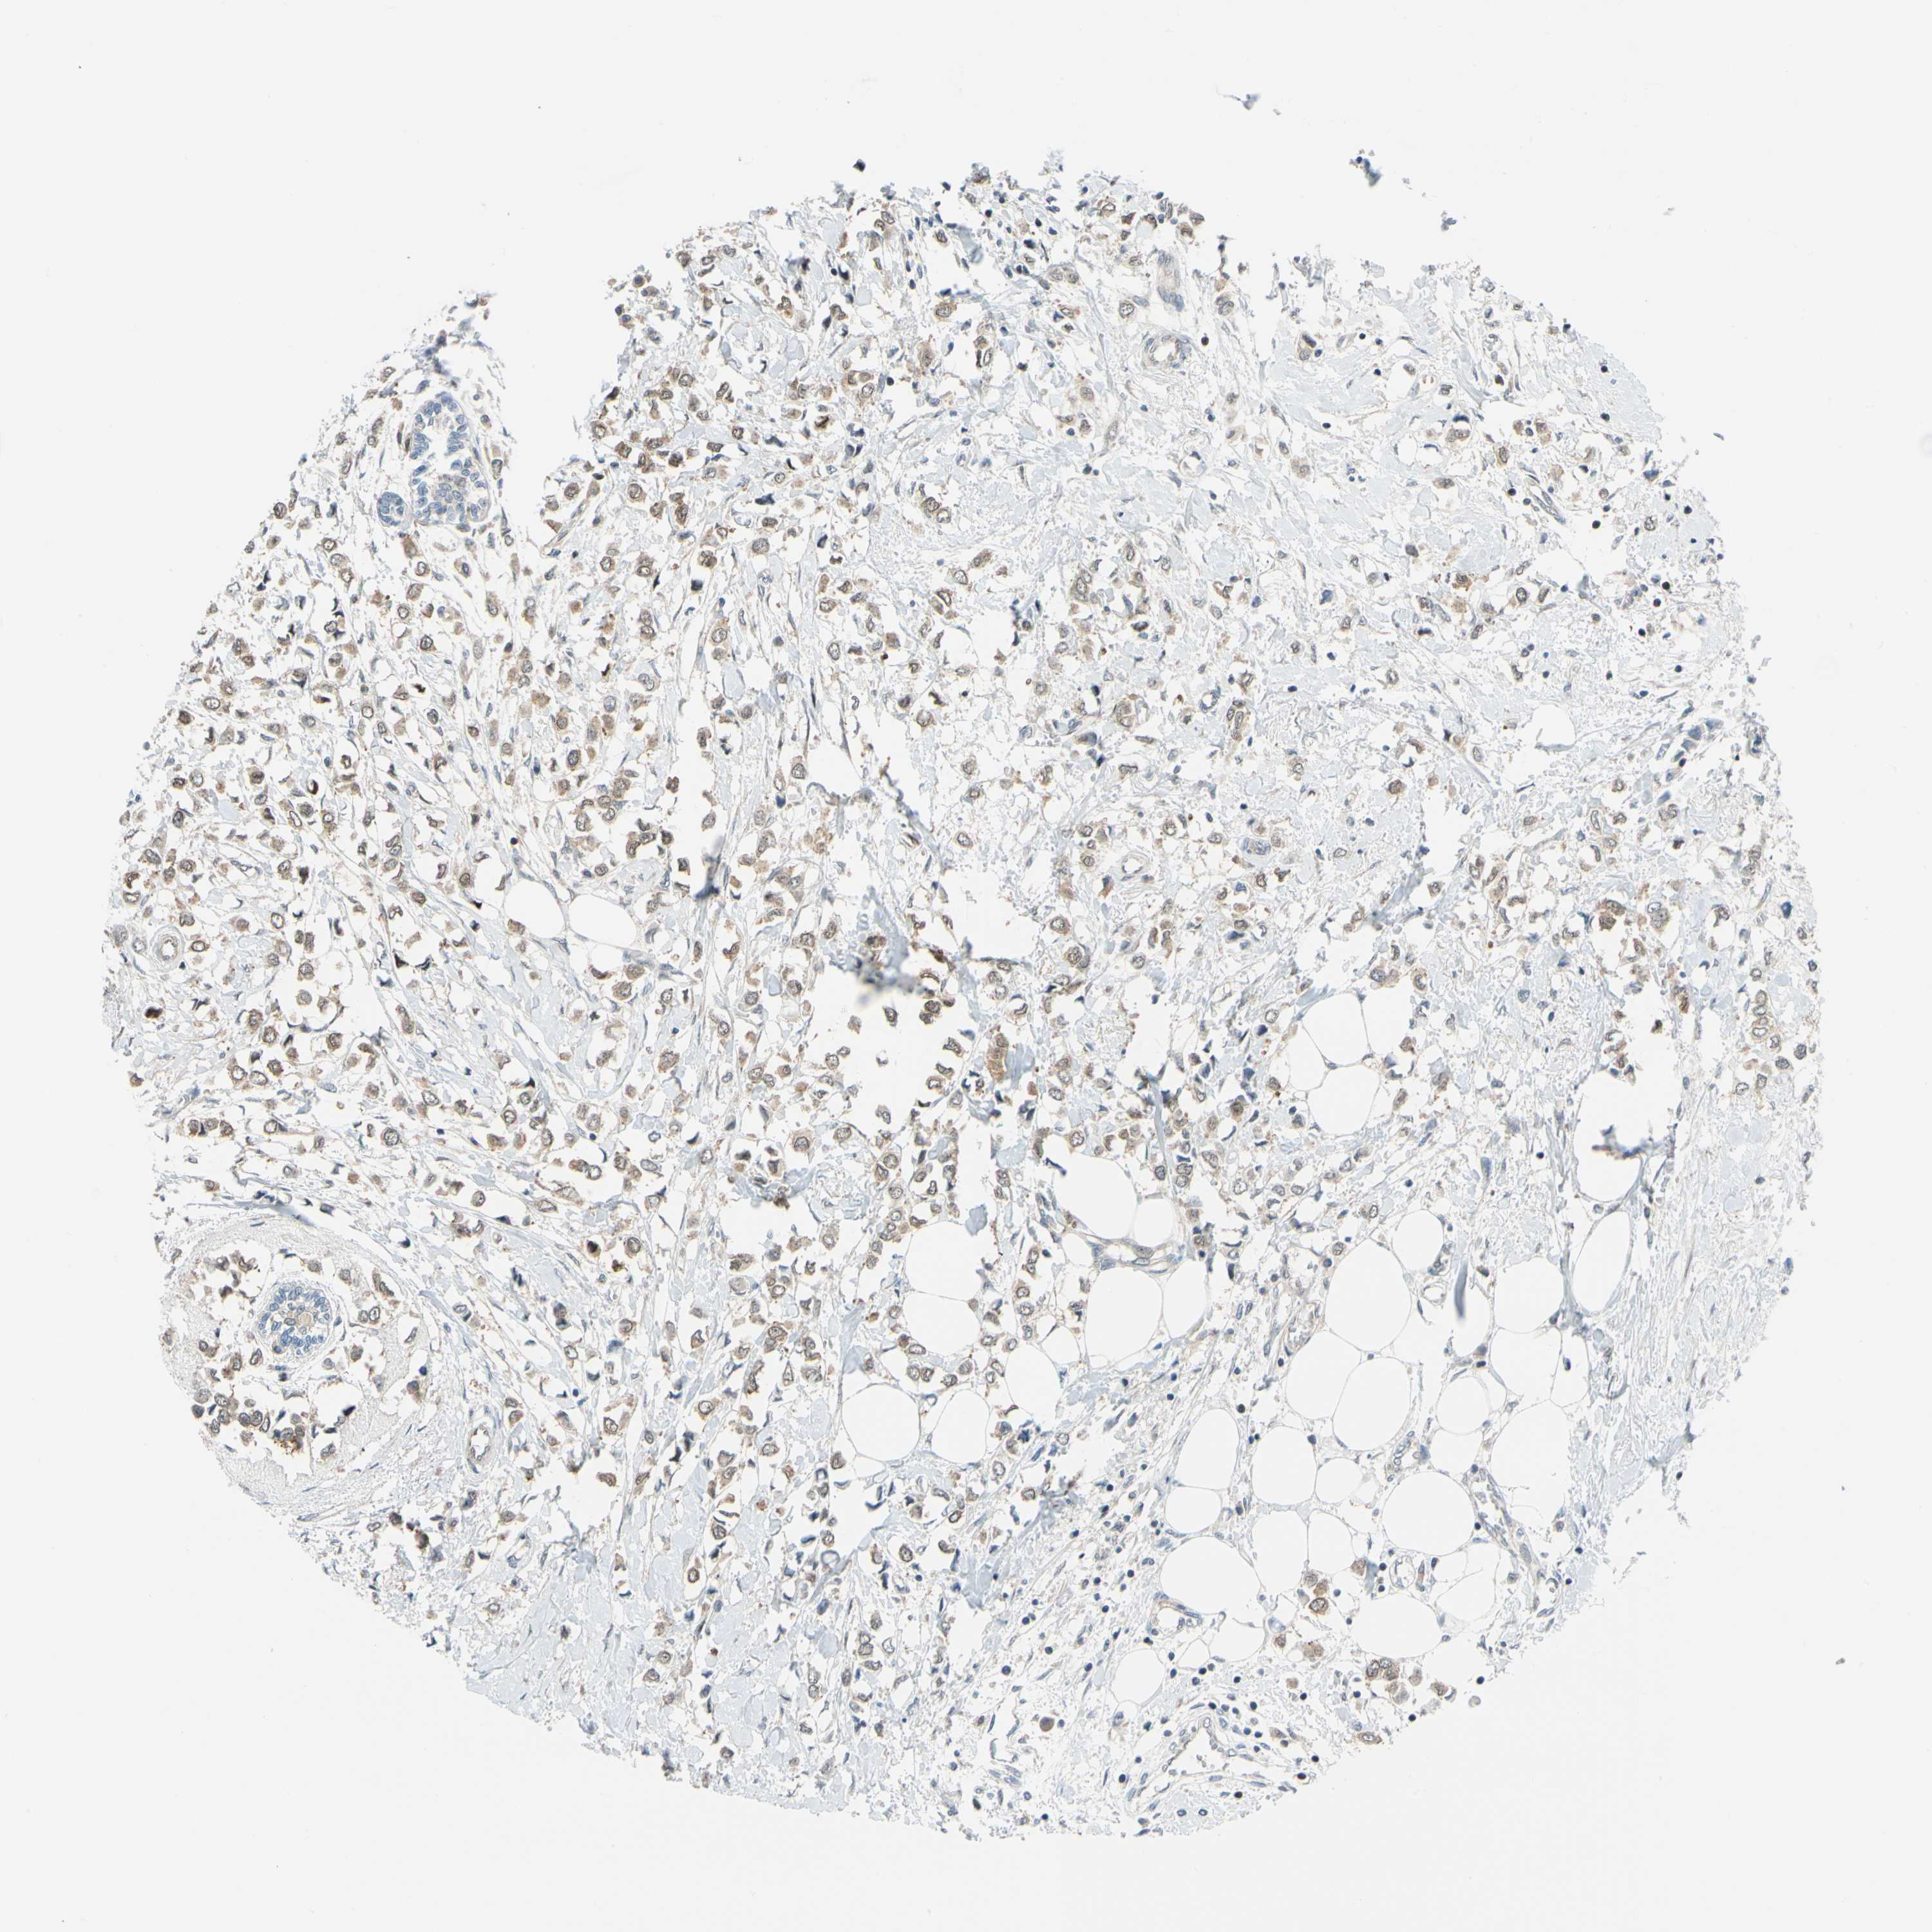

BRCA TCGA BRCA VALIDATION PROTEIN EXPRESSION